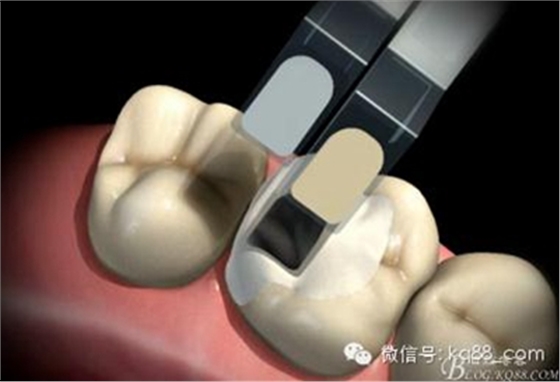

嵌體、高嵌體牙體預備相對簡單,避免倒凹即可

由于邊緣在齦上取印模容易,印模更清晰、更準確

綠標平頭錐形金剛砂牙體初步預備

彎釉質(zhì)鑿去飛邊